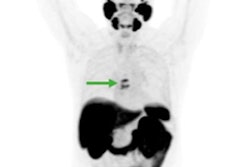

A 72-year-old patient with a prostate-specific antigen (PSA) level of 50.8 ng/ml. The lesion with tumor diameter of 11.7 mm (arrow) was evaluated as positive (PI-RADS score 4) on bpMRI with T2WI image (A), DWI image (B), and ADC map (C), indicating prostate cancer lesion. On F-18 PSMA-1007 PET image (D), the lesion showed intense uptake with an SUVmax of 79.6 (PSMA-RADS score 5). Combined with bpMRI and PET score, fused F-18 PSMA-1007 PET/MRI image (E) further suggested prostate cancer. Subsequent biopsy results (F) proved prostate cancer lesion of ISUP grade 5 with Gleason score 5+4. Image courtesy of Prostate International.Out of the 48 suspected prostate cancer lesions in 29 patients, 38 were identified with biopsies as clinically significant prostate cancer, and 10 were noncancerous lesions. Against these pathological results, F-18 PSMA-1007 PET/MRI demonstrated much greater diagnostic accuracy (area under the curve [AUC]), sensitivity, specificity, positive predictive value (PPV), and negative predictive value (NPV) than bpMRI, the researchers found.